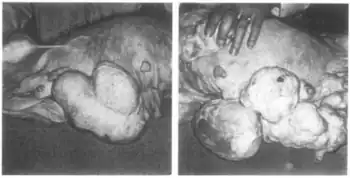

In combination with mestranol, similarly to ethynerone and anagestone acetate (and certain other progestogens, including progesterone and several other 17α-hydroxyprogesterone derivatives), chloroethynylnorgestrel was found to produce striking mammary tumors in beagle dogs after administration at very high dosages (10- to 25-fold human clinical dosages) for prolonged periods of time.[1][3][4] This resulted in the discontinuation of its development, along with that of ethynerone and anagestone acetate, as well as the removal of several progestins, including chlormadinone acetate, medroxyprogesterone acetate, and megestrol acetate, from various markets as contraceptives (although medroxyprogesterone acetate has since been reintroduced).[1][5] Subsequent research revealed that the risk is species-dependent and unique to canines and that there is no similar risk for humans.[6]